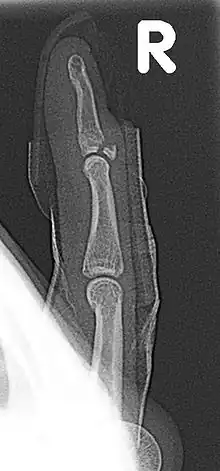

Fracture of the dorsal base of the distal falange by extensor tendon avulsion (Busch fracture)

In medicine a Busch fracture[1] is a type of fracture of the base of the distal phalanx of the fingers, produced by the removal of the bone insertion (avulsion) of the extensor tendon. Without the appropriate treatment, the finger becomes a hammer finger. It would correspond to the group B of the Albertoni classification.[2] It is very common in motorcycle riders and soccer joggers, caused by hyperflexion when the tendon is exercising its maximum tension (the closed hand tightening the clutch lever or the brake lever).[3][4]

The mechanism of this injury can be described as an avulsion of the tendon fixed to the distal phalanx.[6][7][8]

Avulsion of the part of the distal phalanx to which the tendon is attached, a finger fracture

Appearance: the last joint cannot be straightened. See mallet finger